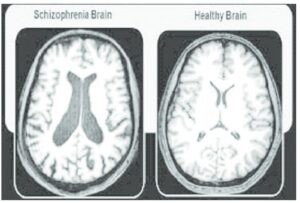

اسکیزوفرنی به طور کلی یک بیماری سلامت روان و اختلال مزمن مغزی است که چندین ناحیه مختلف از مغز را مختل میکند. این بیماری معمولاً بر تفکر، احساسات، استفاده از حواس و رفتار افراد تأثیر میگذارد. افراد مبتلا به اسکیزوفرنی معمولاً در تشخیص واقعیت مشکل دارند. این افراد اغلب دچار توهم و هذیان شده و با تفکرات آشفته دست و پنجه نرم میکنند اما بیماری اسکیزوفرنی پارانوئید چیست؟

- انجام تستهای آزمایشگاهی و تصویربرداری برای بررسی اینکه آیا علائم به دلیل سایر بیماریها یا شرایط پزشکی است یا خیر.